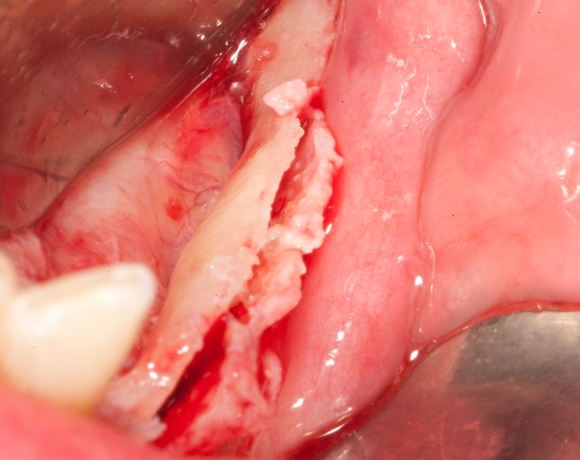

Knochenspaltung Unterkiefer 32 – 36

Die Knochenspaltung auch Bonesplitting genannt, ist eine geeignete Möglichkeit im Unterkieferseitenzahnbereich Knochen aufzubauen, um Implanate setzen zu können. Vorraussetzung ist eine ausreichende Knochenhöhe.

Bei diesem Patientenfall war vor dreizehn Jahren bereits eine Knochenspaltung besprochen

worden, die Patientin hatte allerdings Angst vor dem Eingriff und sich für eine herausnehmbare

Lösung entschieden. Nachdem die endodontisch behandelten Zähne 32 und 33, die mit VMK – Kronen

und Geschiebe versorgt waren, abgebrochen sind, war die Patientin für den Eingriff mit Knochen-

spaltung und drei Implantaten offen. Heute ist sie sehr zufrieden und bereut es nicht gleich diese

Lösung gewählt zu haben.